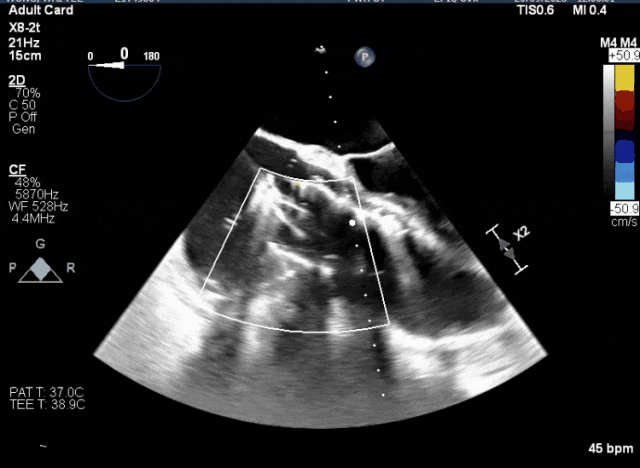

術前超聲顯示三尖瓣重度反流合并拴系

術中TEE成像困難,偽影干擾

術中TEE觀察夾持件的位置

術后超聲評估瓣膜穩定性良好,無瓣周漏